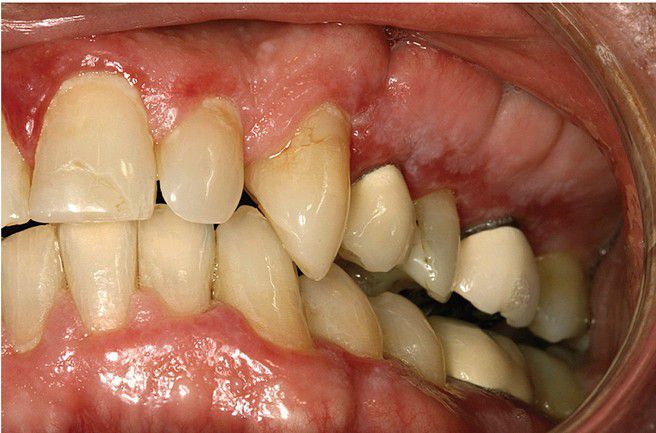

Foreign Body Gingivitis

. Red, atrophic mucosa of the left maxillary facial gingiva. The alterations arose following placement of two porcelain-fused-to-metal (PFM) crowns. Biopsy revealed lichenoid mucositis with intermixed fragments of foreign material.